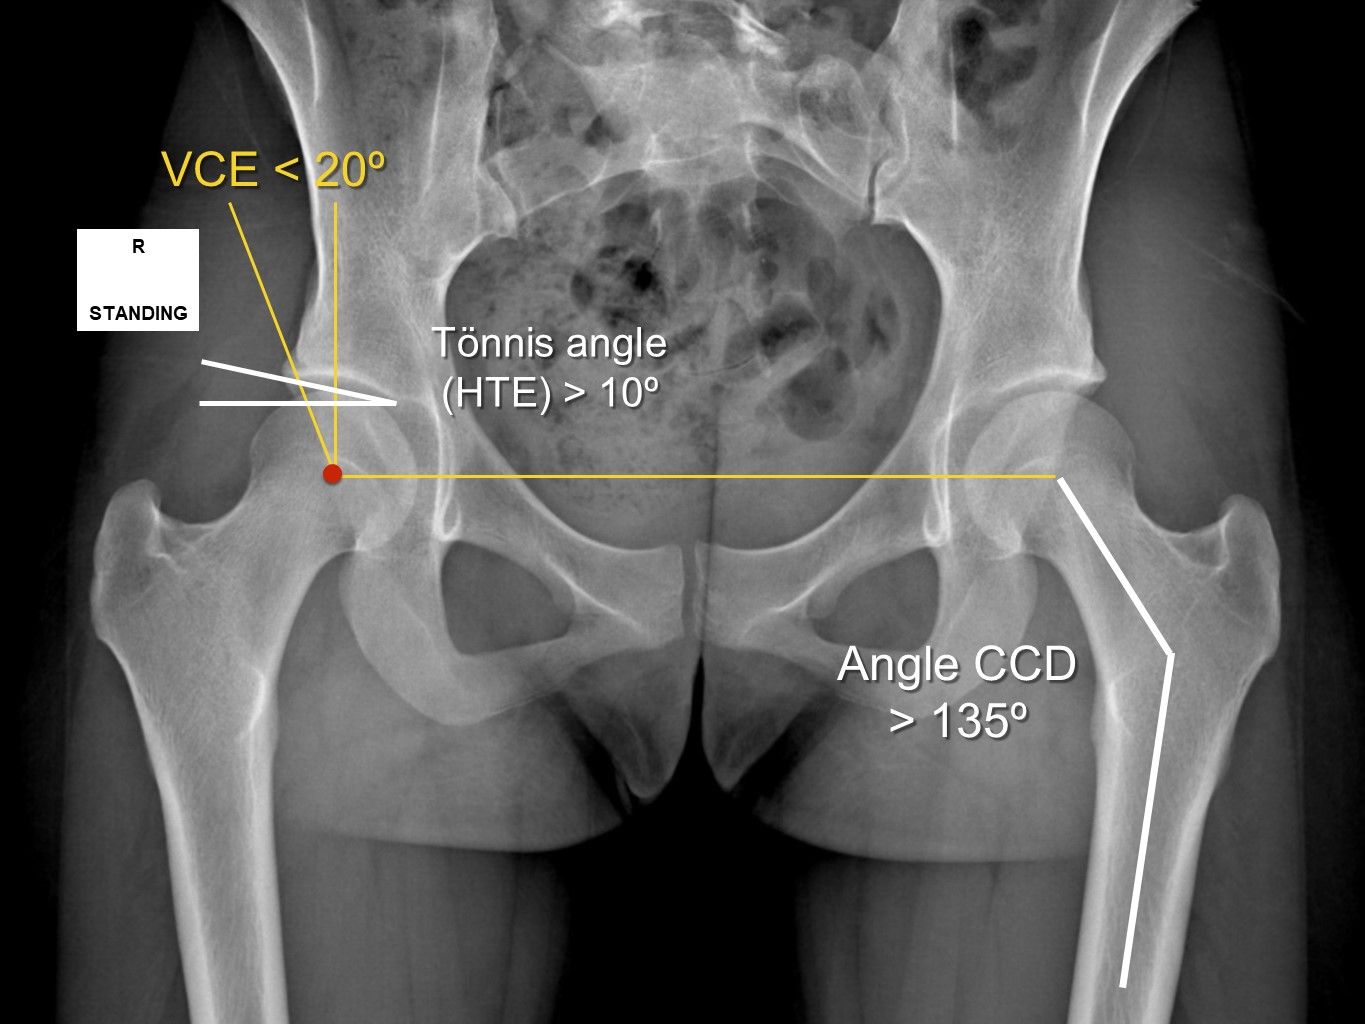

Imaging diagnosis

One can never overestimate the benefits of good standard x-rays and the misery that can be caused by sophisticated but badly performed or misinterpreted tests (CT scans and MRI). The only way to get a perfect assessment is from an expert radiologist working in conjunction with one of the rare orthopaedic surgeons with an interest in this topic (23-25). The first standard x-rays should be standing frontal pelvic views, a Lequesne’s false profile and a Dunn view to assess any accompanying femoroacetabular impingement. The frontal pelvic and false profile views are used to calculate acetabular coverage and identify dysplasia. Coverage less than VCE 25° is suspicious, and an angle of less than 20° as well as a acetabular roof angle > 10° are frankly concerning because it often means that the acetabular bony coverage or position will have to be corrected (Fig. 11). A blunt acetabular rim is also highly suggestive of instability.